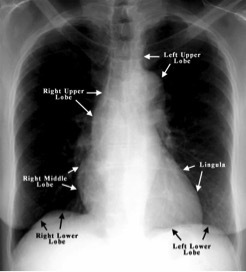

To Differentiate Right from Left:

location of RUL

apical, anterior, & posterior

locate RML

lateral & medial

locate RLL

superior, medial basal, anterior basal, lateral basal, & posterior basal

locate LUL

apical-posterior, anterior, superior lingular, & inferior lingular

o corresponds to RML

o LUL is analogous to RUL and RML combined

locate LLL

superior, medial basal, anterior basal, lateral basal, posterior basal

o LLL is the same as LRL

location of lingular lobes

located in left upper lobe, bordering the heart